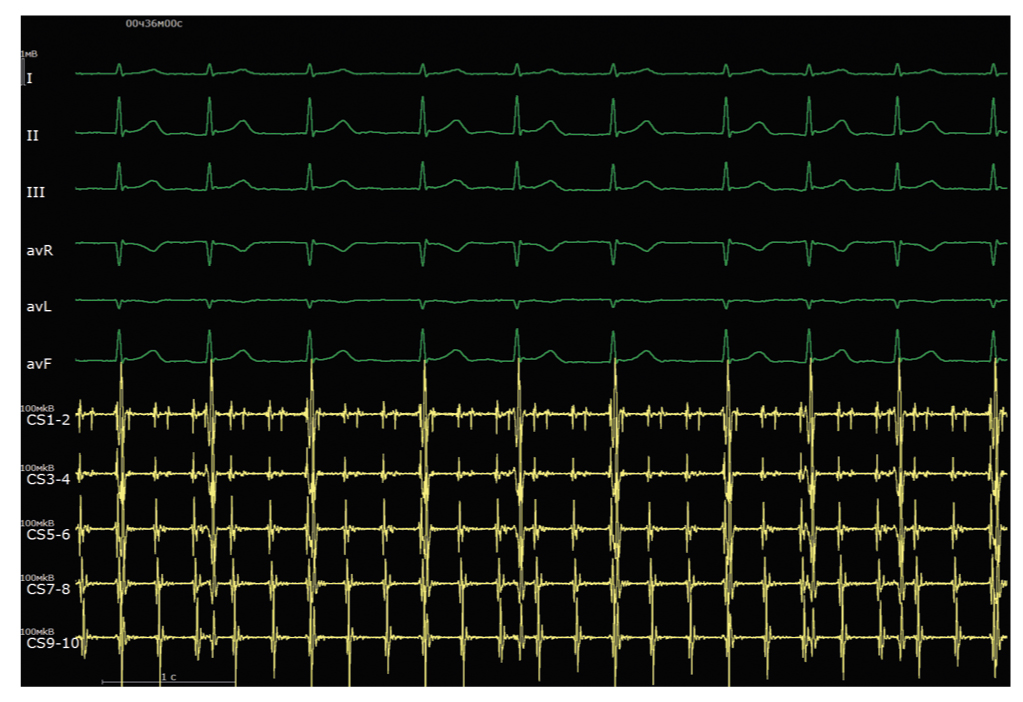

Пациент доставлен в рентгеноперационную. Под комбинированной анестезией ему пунктирована правая бедренная вена и левая подключичная вена. Через интродьюсер, позиционированный в подключичной вене, проведен 10-полюсный диагностический электрод в коронарный синус сердца. По электрофизиологическим данным: на электроде, позиционированном в коронарном синусе, левопредсердное трепетание с длиной цикла тахикардии 290 мс с проведением 2:1 (рис. 1).

Рис. 1. Интраоперационная электрограмма, где I–III, aVL, aVR, aVF — отведения электрокардиограммы, CS (1–10) — запись электрограмм с электрода, размещенного в коронарном синусе. Регистрируется атипичное трепетание предсердий с длиной цикла 290 мс. / Fig. 1. An intraoperative electrogram, where I–III, aVL, aVR, aVF are electrocardiogram leads, CS (1–10) — is recording of electrograms from an electrode placed in the coronary sinus. Atypical atrial flutter with a cycle length of 290 ms is being registered.